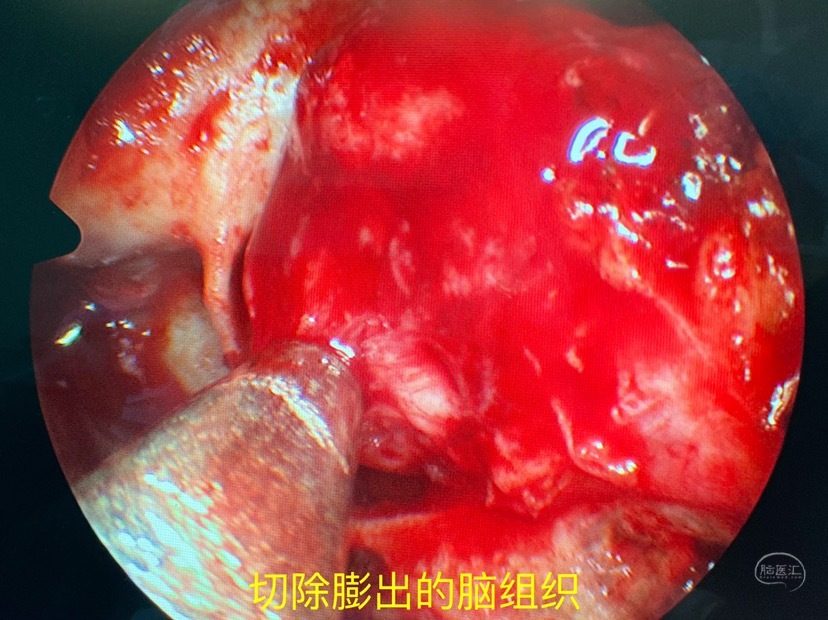

进一步切除膨出物并寻找漏口

找到颅底骨质缺损处

漏口位于颅底侧方区,显露是关键